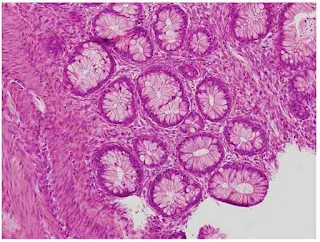

Teratomlar, üreme hücrelerinden (germ hücreleri) gelişen ve iyi huylu veya kötü huylu olabilen nadir tümörlerdir. Genellikle yumurtalık, testis ve kuyruk kemiği gibi bölgelerde görülür. Bazen cilt, diş, kas veya saç gibi farklı doku tiplerini bir arada içerebilirler.

✅ Olgun Teratomlar (Benign)

Katı, kistik veya karışık yapıda olabilir.

Teratomlar, fetal gelişim sırasında hücrelerin farklılaşma sürecinde meydana gelen anormallikler sonucu oluşur. Bu hücreler, normalde gitmemesi gereken bölgelere gidip orada farklı dokular oluşturabilir.